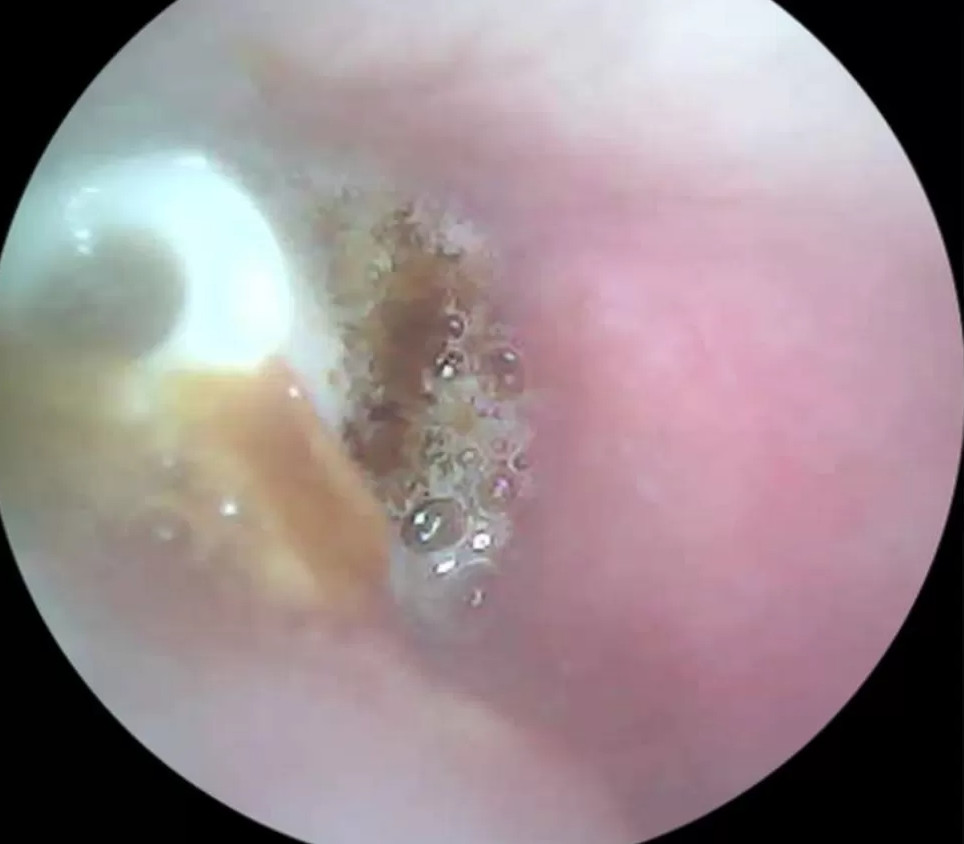

直到華勒斯買了居家掏耳棒內視鏡,他一照驚覺聽不見的那隻耳朵裡有塊白色異物,才趕快去看醫生。華勒斯表示耳朵是搭飛機時塞住的:「5年前我飛去澳洲探親就買了小耳塞,可以依照抗噪等級塞入不同的配件,結果其中一個小耳塞被留在裡面沒拿出來。」

翻攝自Wallace Lee。

耳鼻喉科醫師治療時本來想將耳塞吸出來,不過因為它已經卡了5年,旁邊都被耳垢堵住完全無動於衷,所以醫師改用小型鑷子進入耳道將異物拉出來。華勒斯非常驚喜:「我可以感覺到他在拉扯,然後『啵』一聲,房間裡的聲音我都聽得一清二楚了!多年困擾瞬間煙消雲散,我現在聽力非常好,真是鬆了一大口氣!」耳鼻喉科醫師尼爾·德佐伊薩 (Neil De Zoysa) 呼籲民眾若發現耳朵有異物千萬別自行亂掏,最好尋求專業醫療協助,以免引發感染或是增加治療難度。